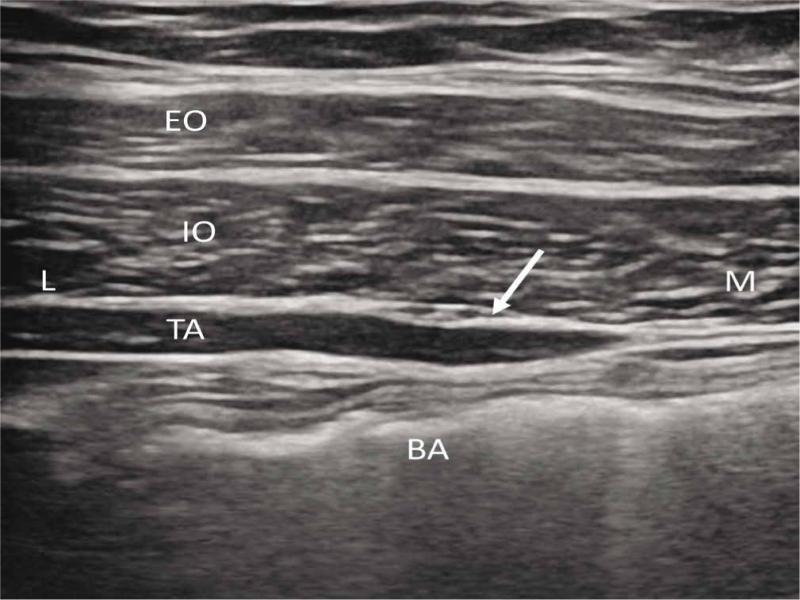

Fig. 3.